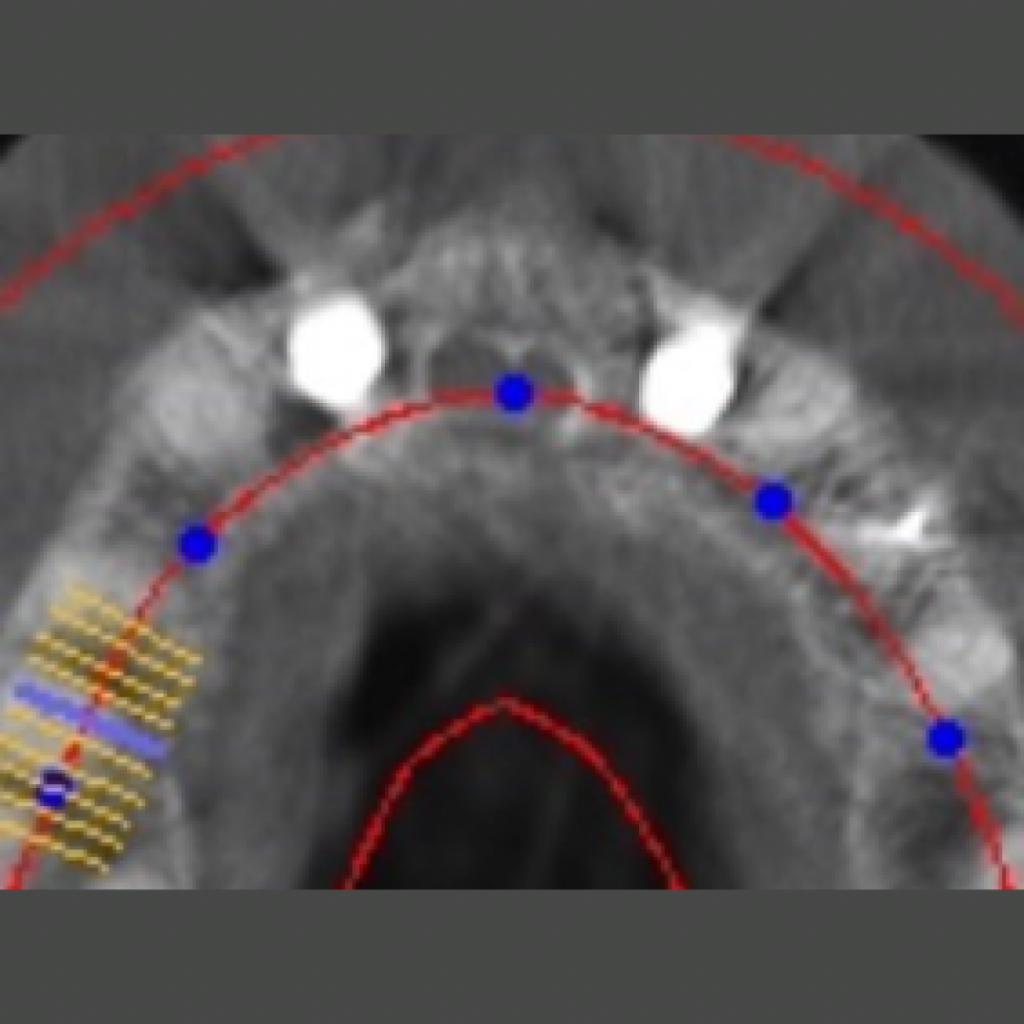

Имплантация AnyOne в узкий гребень. Восстановление зубов 11,12,21,22 на двух имплантатах.